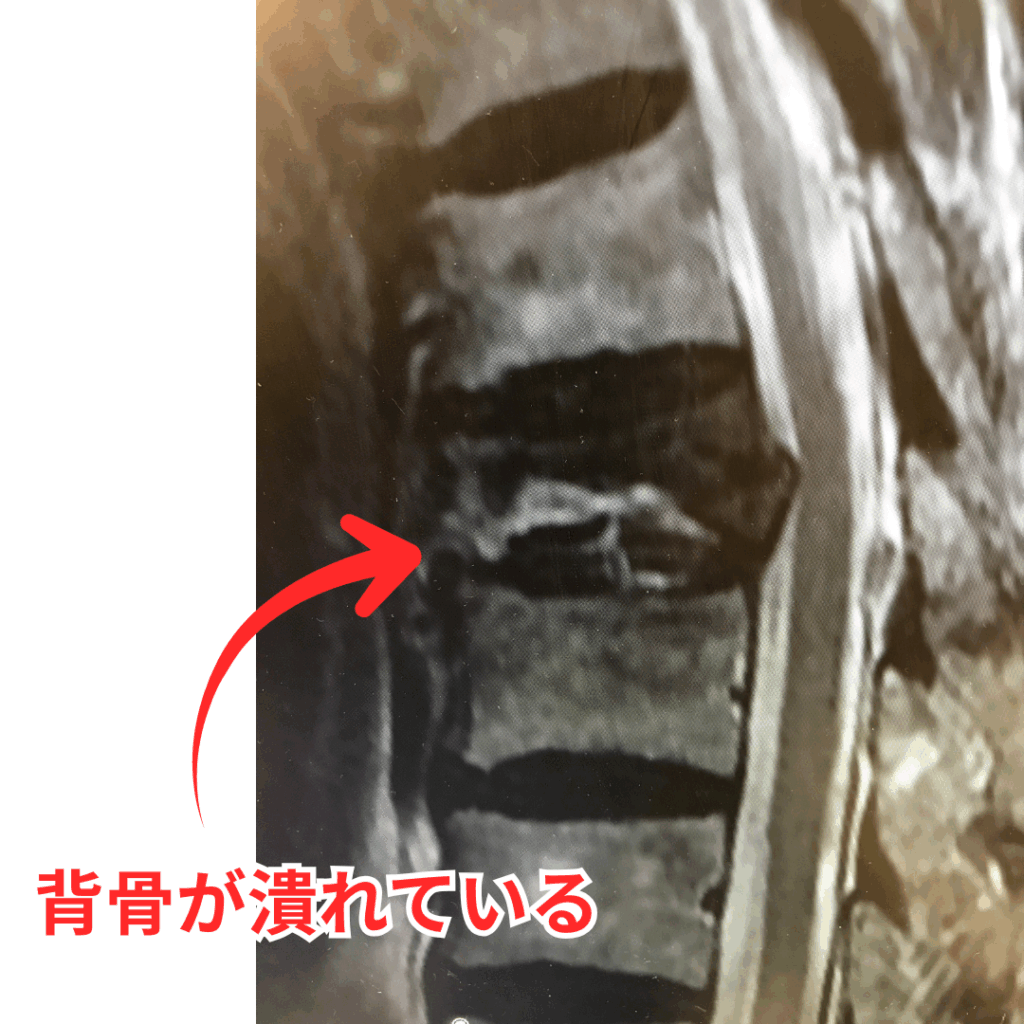

実は腰痛の多くは、レントゲンやMRIなどの検査で原因が特定できないことが多くあります。

医学的には

特異的腰痛(約15%)

原因が明確に分かる腰痛

非特異的腰痛(約85%)

原因を一つに特定できない腰痛

と分類されています。

つまり多くの腰痛は

画像に写らない負担が関係しているケースです。

このような状態はレントゲンやMRIには写らないため、原因がはっきりしない腰痛として扱われることも少なくありません。